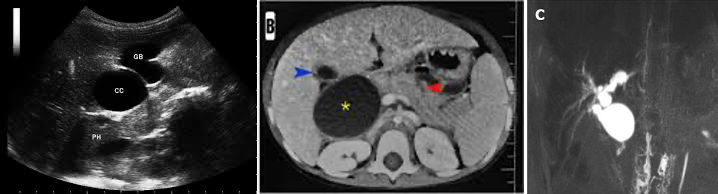

총담관낭

• 정의: 담관이 선천적으로 낭성으로 확장되는 질환

• TRIAD: 황달, RUQ pain, RUQ mass

• 진단: 영상학적 진단 (복부 초음파, CT, MRCP/ERCP/PTC)

• 치료: cyst 절제 + hepaticojejunostomy